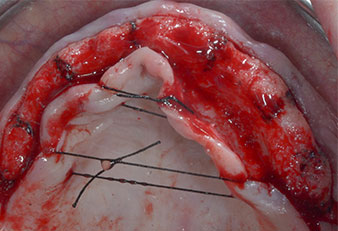

Wegen des relativ harten Knochens (D2) an den Positionen 11 und 21 wurden die 10 mm langen Implantatlager in diesem Bereich abschließend mit einem 4-mm-Spiralbohrer, dem chirurgischen Winkelstück WS-75 L von W&H und dem W&H Implantmed Implantologiemotor in Verbindung mit dem optionalen W&H Osstell ISQ module präpariert. Im Gegensatz dazu wurde der weiche Knochen der Implantatlager im Seitenzahnbereich mit dem Piezomed I3P auf den abschließenden Durchmesser von 3 mm erweitert. Die Implantate wurden dann transgingival eingesetzt, die Einheildauer betrug drei Monate (Abb. 6-10). Die vorhandene Prothese wurde auf vier provisorischen Implantaten abgestützt (Abb. 8).